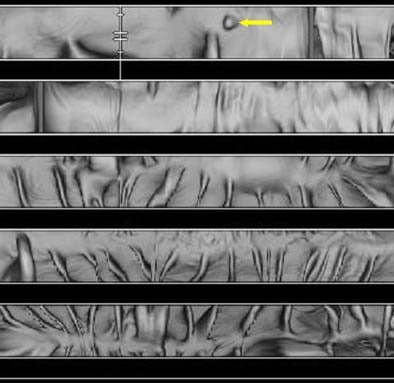

| Virtual colonic dissection (VCD) shows a 5-mm sessile rectal polyp (arrow). VCD creates a 3-D panel of the inner colonic surface. The left upper corner represents the most aboral and the right lower corner the most oral portion of the colon. Image courtesy of Dr. Hanno Hoppe. |

The VCD software package opens up and unfolds the colon virtually, and visualizes its internal surface in three dimensions, Hoppe said. "For use of virtual colon dissection, first a central colonic path needs to be defined within the colon dataset. Second, the virtual colon is unfolded along this longitudinal axis, and so the surface of the colon is visualized in 3-D. Once the center part of the colon is defined, the software generates a panel of the inner view of the colonic surface.... This panel has a field of view of 90° , and in order to view the entire mucosal surface, you can shift the field of view in increments of 45° ."